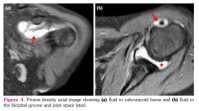

Also, MRI revealed significant joint effusion in 9/32 (28.1%) joints in six patients (Figure 4a, b). Eight of these nine joints had ≥1 JAMRIS component of MRI finding (Supplemental Table 1). Six of these nine joints had synovial hypertrophy (Grade I- 1 joint, and Grade II- 5 joints). Four joints each showed cartilage lesions and bone erosions, respectively. Bone marrow edema was seen in seven joints. It was also noted that six (66%) of the nine joints (4 patients) that had effusion did not fulfil the definition of clinical arthritis.

In addition, the presence or absence of synovial effusion on MRI was also noted. Joint effusion was seen as hyperintensity adjacent to synovium on post-contrast T1-weighted images.